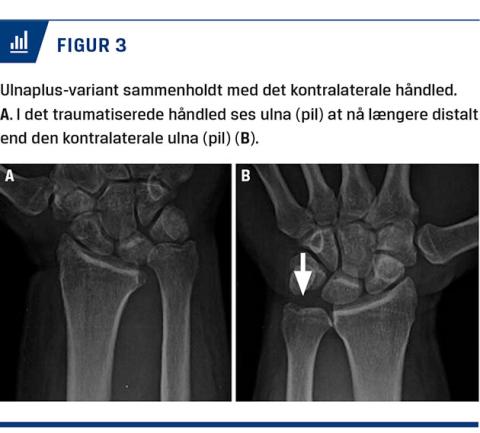

Ved begrundet mistanke om proksimal glidning af radius skal der suppleres med en røntgenoptagelse af håndleddet, der i så fald vil præsentere en vis grad af ulnaplusvariant (Figur 3) og eventuelt en dorsal luksation af ulna.

Det er endnu usikkert, hvilken del af ELL, der forekommer først, men ved tilstrækkelig aksial belastning vil caput radii frakturere mod capitulum, og IOM vil revne på tværs af fibrene. Dette medfører tab af de to vigtigste aksiale stabilisatorer i underarmen [1] og vil afstedkomme en akut eller gradvis luksation i DRUJ og følgende proksimal glidning af radius. Den proksimale glidning af radius vil resultere i en såkaldt ulnaplusvariant i håndleddet, hvilket i sig selv er forbundet med risiko for at få kroniske smerter [2].